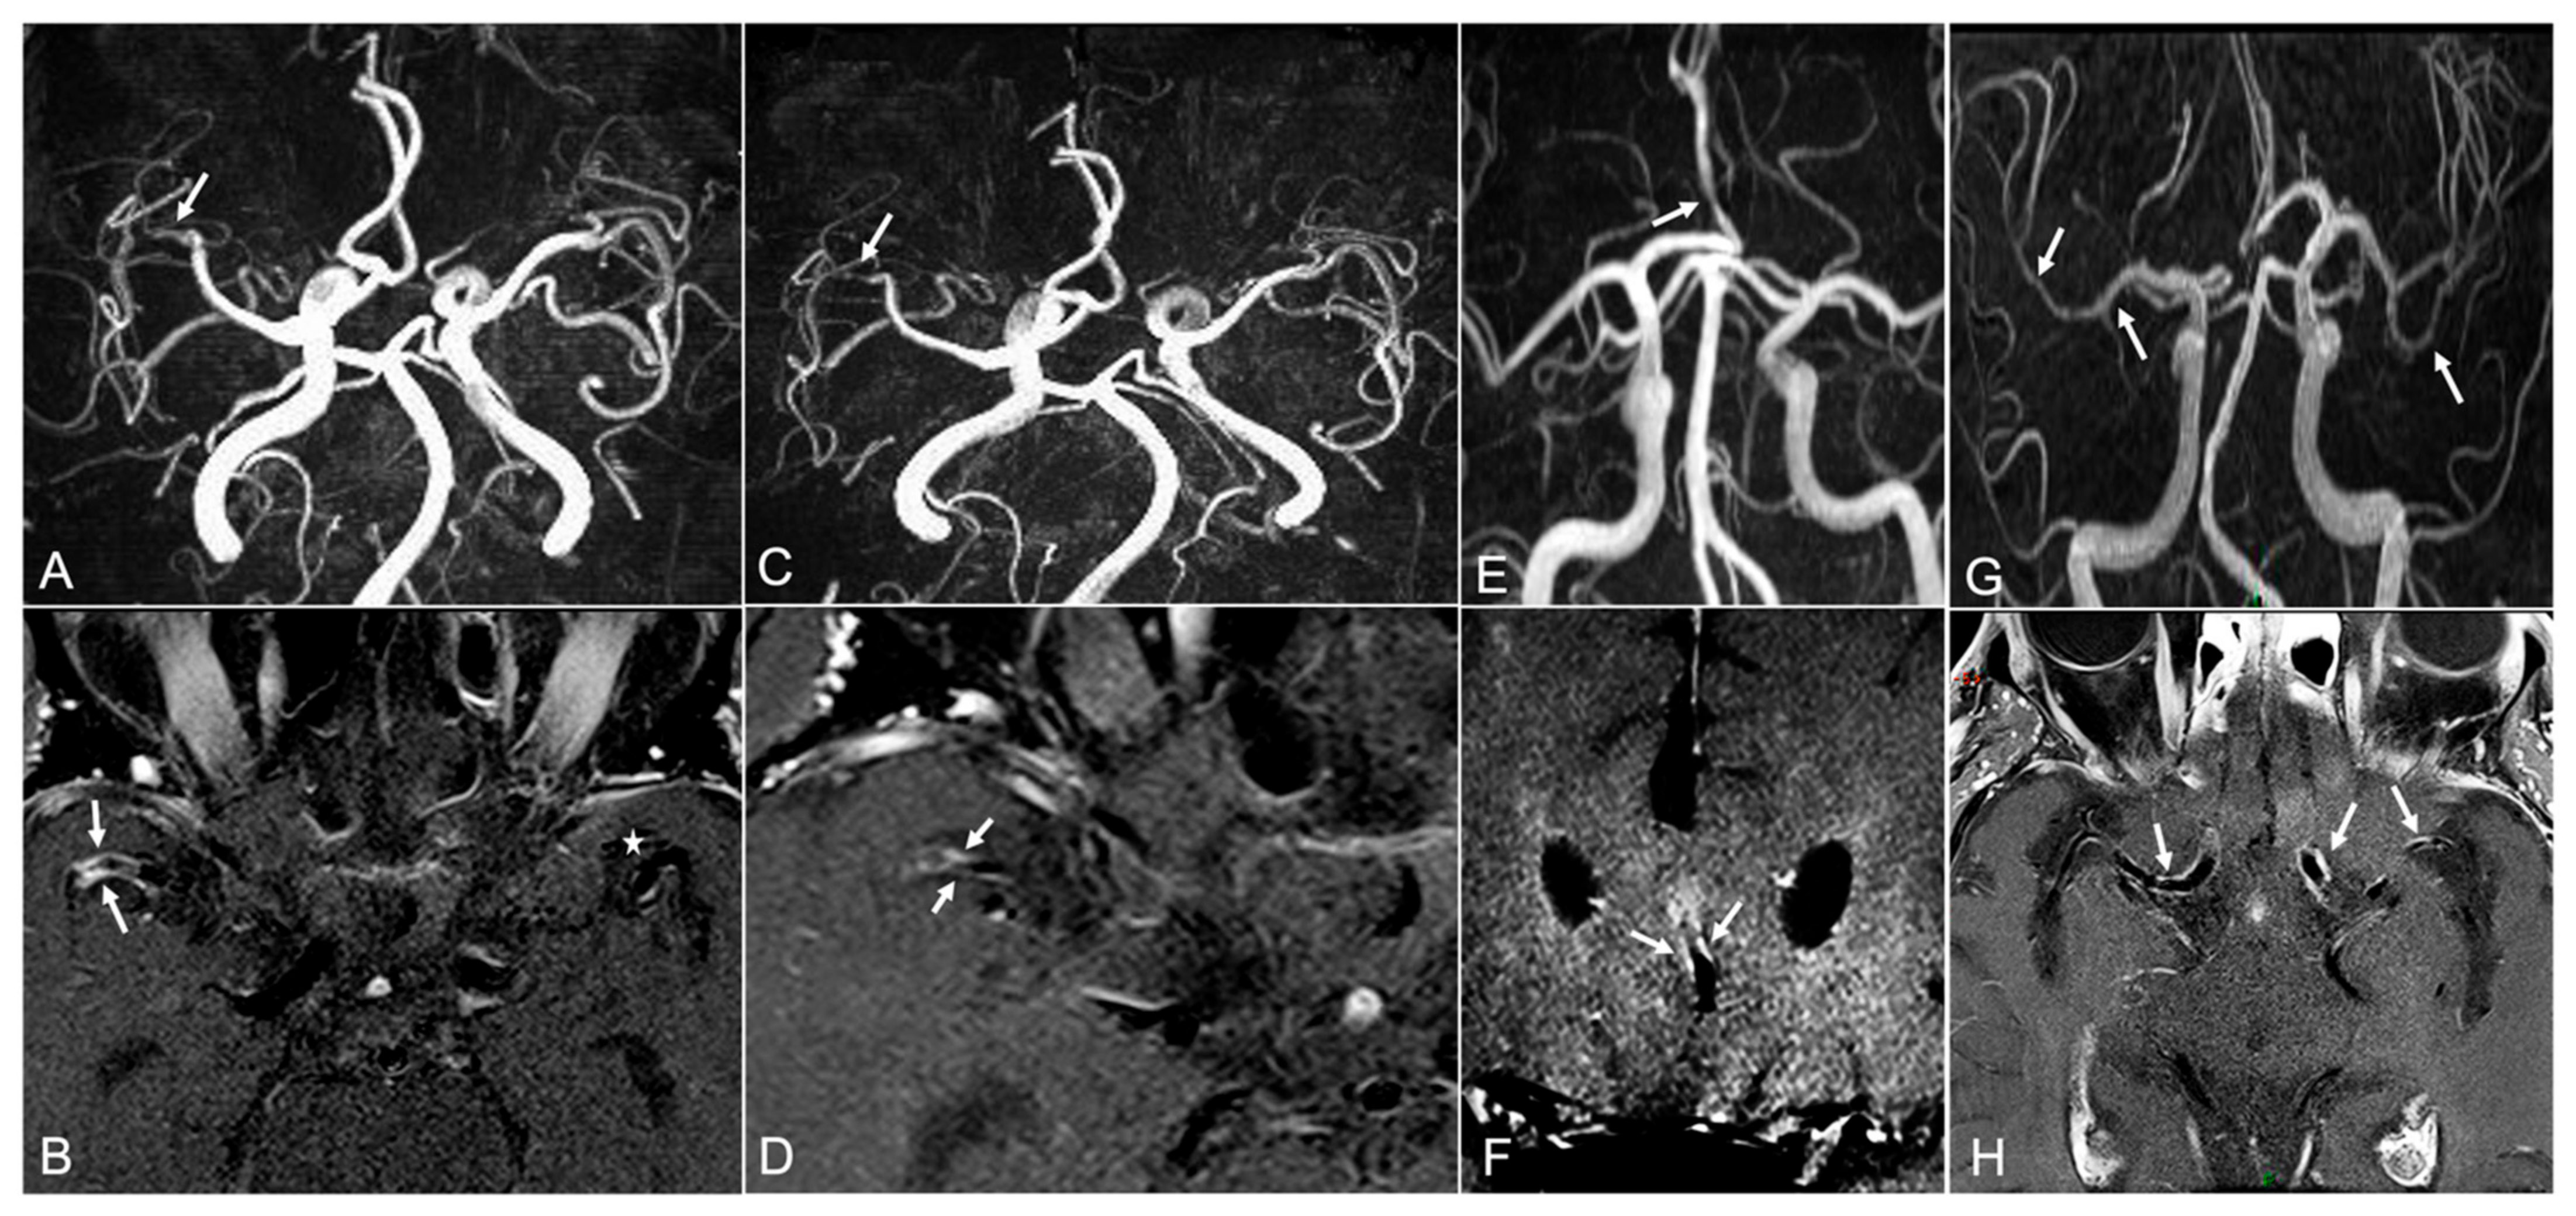

- Mossa-Basha, M.; de Havenon, A.; Becker, K.J.; Hallam, D.K.; Levitt, M.R.; Cohen, W.A.; Hippe, D.S.; Alexander, M.D.; Tirschwell, D.L.; Hatsukami, T.; et al. Added Value of Vessel Wall Magnetic Resonance Imaging in the Differentiation of Moyamoya Vasculopathies in a Non-Asian Cohort. Stroke 2016, 47, 1782–1788. [Google Scholar] [CrossRef] [Green Version]

- Kim, Y.J.; Lee, D.H.; Kwon, J.Y.; Kang, D.W.; Suh, D.C.; Kim, J.S.; Kwon, S.U. High resolution MRI difference between moyamoya disease and intracranial atherosclerosis. Eur. J. Neurol. 2013, 20, 1311–1318. [Google Scholar] [CrossRef]

- Ryoo, S.; Cha, J.; Kim, S.J.; Choi, J.W.; Ki, C.-S.; Kim, K.H.; Jeon, P.; Kim, J.-S.; Hong, S.-C.; Bang, O.Y. High-resolution magnetic resonance wall imaging findings of Moyamoya disease. Stroke 2014, 45, 2457–2460. [Google Scholar] [CrossRef] [PubMed] [Green Version]